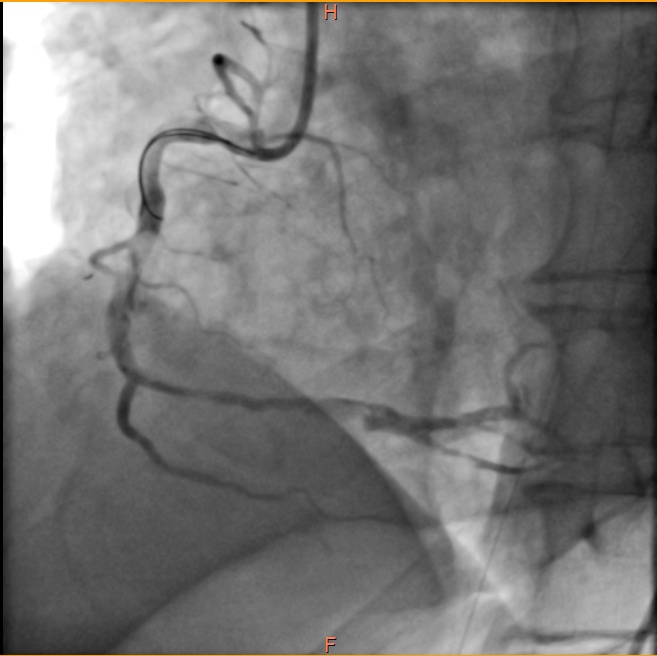

通过反复抽吸血栓并注射抗血栓药物,闭塞的血管再次有血流通过,病人心率、血压也稳定了下来。

(血栓抽吸后血管远段显影)